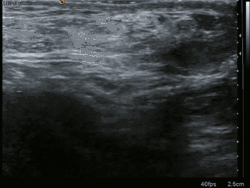

Ultrasound image of inguinal hernia. Moving intestines in the inguinal canal with respiration.

Medical imaging

A physician may diagnose an inguinal hernia, as well as the type, from medical history and physical examination.[20] For confirmation or in uncertain cases, medical ultrasonography is the first choice of imaging, because it can both detect the hernia and evaluate its changes with for example pressure, standing and Valsalva maneuver.[21]

When assessed by ultrasound or cross sectional imaging with CT or MRI, the major differential in diagnosing indirect inguinal hernias is differentiation from spermatic cord lipomas, as both can contain only fat and extend along the inguinal canal into the scrotum.[22]